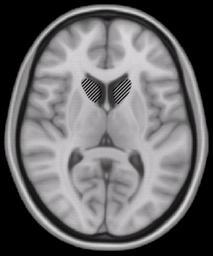

MAKE A MEME View Large Image Caudate nucleus.jpg en Caudate nucleus Part of the basal ganglia which is part of the brain Own Woutergroen 2008 Magnetic resonance imaging of the brain Caudate nucleus

Keywords: Caudate nucleus.jpg en Caudate nucleus Part of the basal ganglia which is part of the brain Own Woutergroen 2008 Magnetic resonance imaging of the brain Caudate nucleus